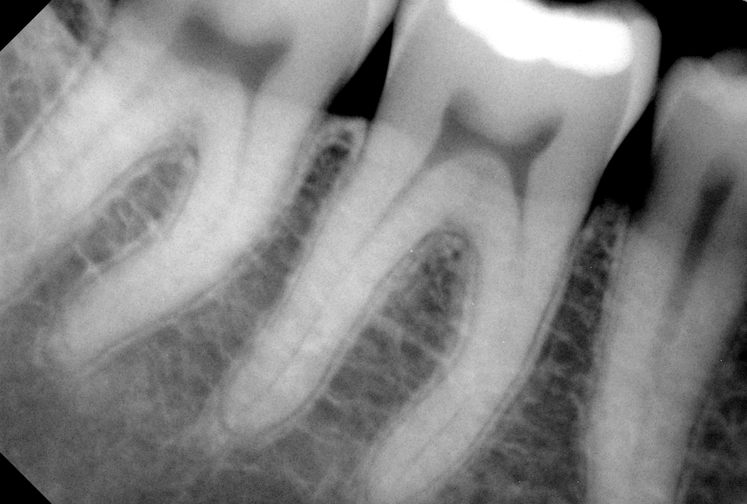

Стоматологические Исследования: Рентген Инвагинации Зубов